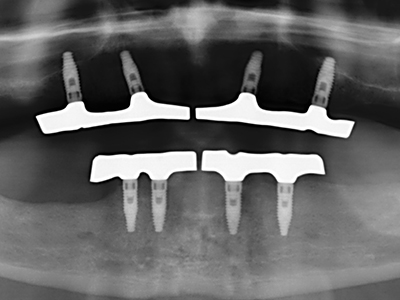

For removal of an implant, a vestibular bone cover that is replaced after removal of the implant screw can be prepared to retain the contour of the alveolar ridge.